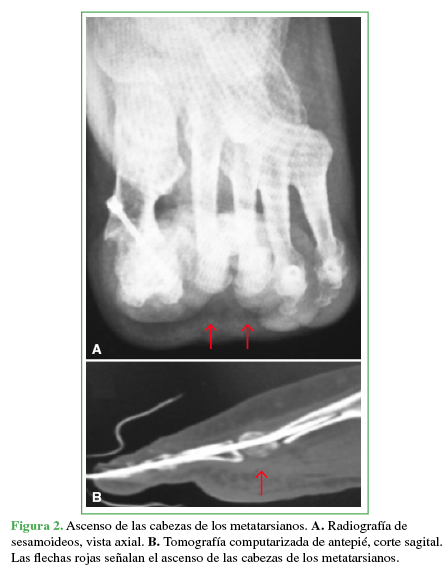

A continuación, se realiza la OMDP en la metáfisis distal con un ángulo aproximado de 45° en relación con el piso. Esta se efectúa de distal dorsal a proximal plantar para lograr el ascenso y acortamiento de la cabeza del metatarsiano, finalmente se avanza la clavija de Kirschner hacia la diáfisis del metatarsiano (Figura 1). Así, se busca disminuir la presión ejercida por las cabezas metatarsianas contra el piso (Figura 2). Por otra parte, se eleva el centro de rotación para que los músculos intrínsecos actúen nuevamente como flexores de la articulación metatarsofalángica, intentando disminuir la incidencia de dedo flotante. Para finalizar se realiza la tenotomía percutánea del flexor largo del dedo tratado para prevenir la posterior progresión a dedo en mazo.

Los pacientes fueron evaluados clínica y radiológicamente antes de la cirugía, a las 3 semanas, a los 3 meses, o hasta constatar la consolidación (Figuras 3 y 4).